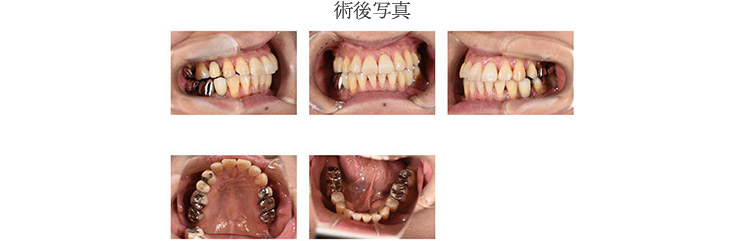

зҹӯгҒ„жҷӮй–“гҒ§жӯЈзўәгҒӘжІ»зҷӮгӮ’иЎҢгҒӘгҒҶгҒҹгӮҒгҒ«гҒҜгҖҒе…ҘеҝөгҒӘиЎ“еүҚжә–еӮҷгҒҢж¬ гҒӢгҒӣгҒҫгҒӣгӮ“гҖӮеҪ“йҷўгҒ§гҒҜдәӢеүҚгҒ«гӮігғігғ”гғҘгғјгӮҝгғјгҒ«гӮҲгӮӢгӮ·гғҹгғҘгғ¬гғјгӮ·гғ§гғігӮ’иЎҢгҒӘгҒ„гҖҒжӯҜ科еҢ»её«гҒ®жүӢгҒ®ж„ҹиҰҡгҒЁеӢҳгҒ«й јгӮӢгғ•гғӘгғјгғҸгғігғүгҒ§гҒҜгҒӘгҒҸгҖҒгӮ¬гӮӨгғүгӮ’дҪҝгҒҶгҒ“гҒЁгҒ§еҲҮй–ӢгҒҷгӮӢйғЁеҲҶгӮ’жңҖе°ҸйҷҗгҒ«жҠ‘гҒҲгҖҒгӮҲгӮҠзІҫеҜҶгҒ§й«ҳеәҰгҒӘжІ»зҷӮгӮ’е®ҹзҸҫгҒ•гҒӣгҒҰгҒ„гҒҫгҒҷгҖӮ

гӮөгғјгӮёгӮ«гғ«гӮӘгғҡгҒ«гӮҲгӮӢгӮ¬гӮӨгғүгӮӘгғҡгҒ«гҒӨгҒ„гҒҰ

е®үеҝғе®үе…ЁгҒӘгӮӨгғігғ—гғ©гғігғҲгҒ®жӨҚз«ӢгҒ®зӮәгҒ«дәҲгӮҒCTгҒ®ж’®еҪұгҖҒгӮҪгғ•гғҲдёҠгҒ§гӮ·гғҘгғҹгғ¬гғјгӮ·гғ§гғігӮ’иЎҢгҒ„гҖҒгҒқгӮҢгҒ«еҹәгҒҘгҒ„гҒҰ3Dгғ—гғӘгғігӮҝгғјгҒ§гӮөгғјгӮёгӮ«гғ«гӮ¬гӮӨгғүгӮ’дҪңгҒЈгҒҰжүӢиЎ“гӮ’иЎҢгҒ„гҒҫгҒҷгҖӮ гҒқгҒ®зөҗжһңгҖҒиҝ…йҖҹгҒӢгҒӨжӯЈзўәгҒӘгӮӘгғҡгҒҢеҸҜиғҪгҒЁгҒӘгӮҠгҒҫгҒҷгҖӮгҒҫгҒҹзё«еҗҲгҒ®еҝ…иҰҒгӮӮгҒӘгҒ„гҒҹгӮҒгҖҒдҪ“гҒёгҒ®иІ жӢ…гӮ’жҠ‘гҒҲгӮӢгҒ“гҒЁгҒҢгҒ§гҒҚгҒҫгҒҷгҖӮ